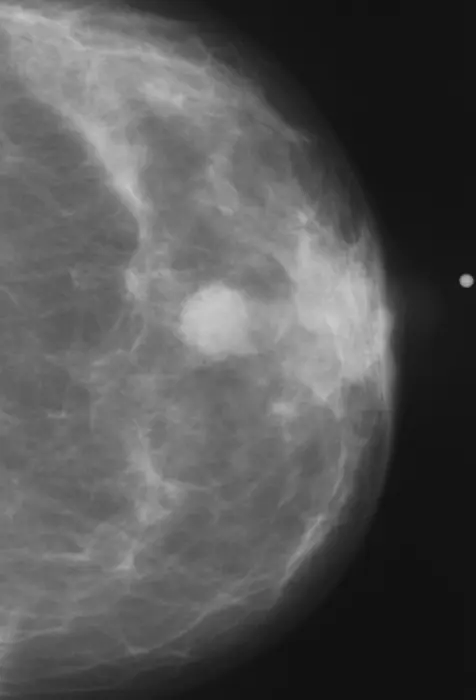

ABNORMAL MAMMOGRAM.

view moreCREDIT: RSNA

CHICAGO – A deep learning artificial intelligence (AI) model that was developed using only mammogram image biomarkers accurately predicted both ductal carcinoma in situ (DCIS) and invasive carcinoma, according to research being presented today at the annual meeting of the Radiological Society of North America (RSNA). Additionally, the model showed no bias across multiple races.

A deep learning AI risk assessment model developed using mammographic images alone can outperform traditional risk assessment models in future breast cancer development while also mitigating the racial biases seen in traditional models.

“The model is able to translate the full diversity of subtle imaging biomarkers in the mammogram, beyond what the naked eye can see, that can predict a woman’s future risk of both DCIS and invasive breast cancer,” Dr. Lamb said. “The deep learning image-only risk model can provide increased access to more accurate, equitable and less costly risk assessment.”

The predictive rate of both DCIS and invasive cancer was 0.71 across all races. The AUC in predicting DCIS was 0.77 in non-white patients and 0.71 in white patients. The AUC in predicting invasive cancer was 0.72 in non-white patients and 0.71 in white patients.